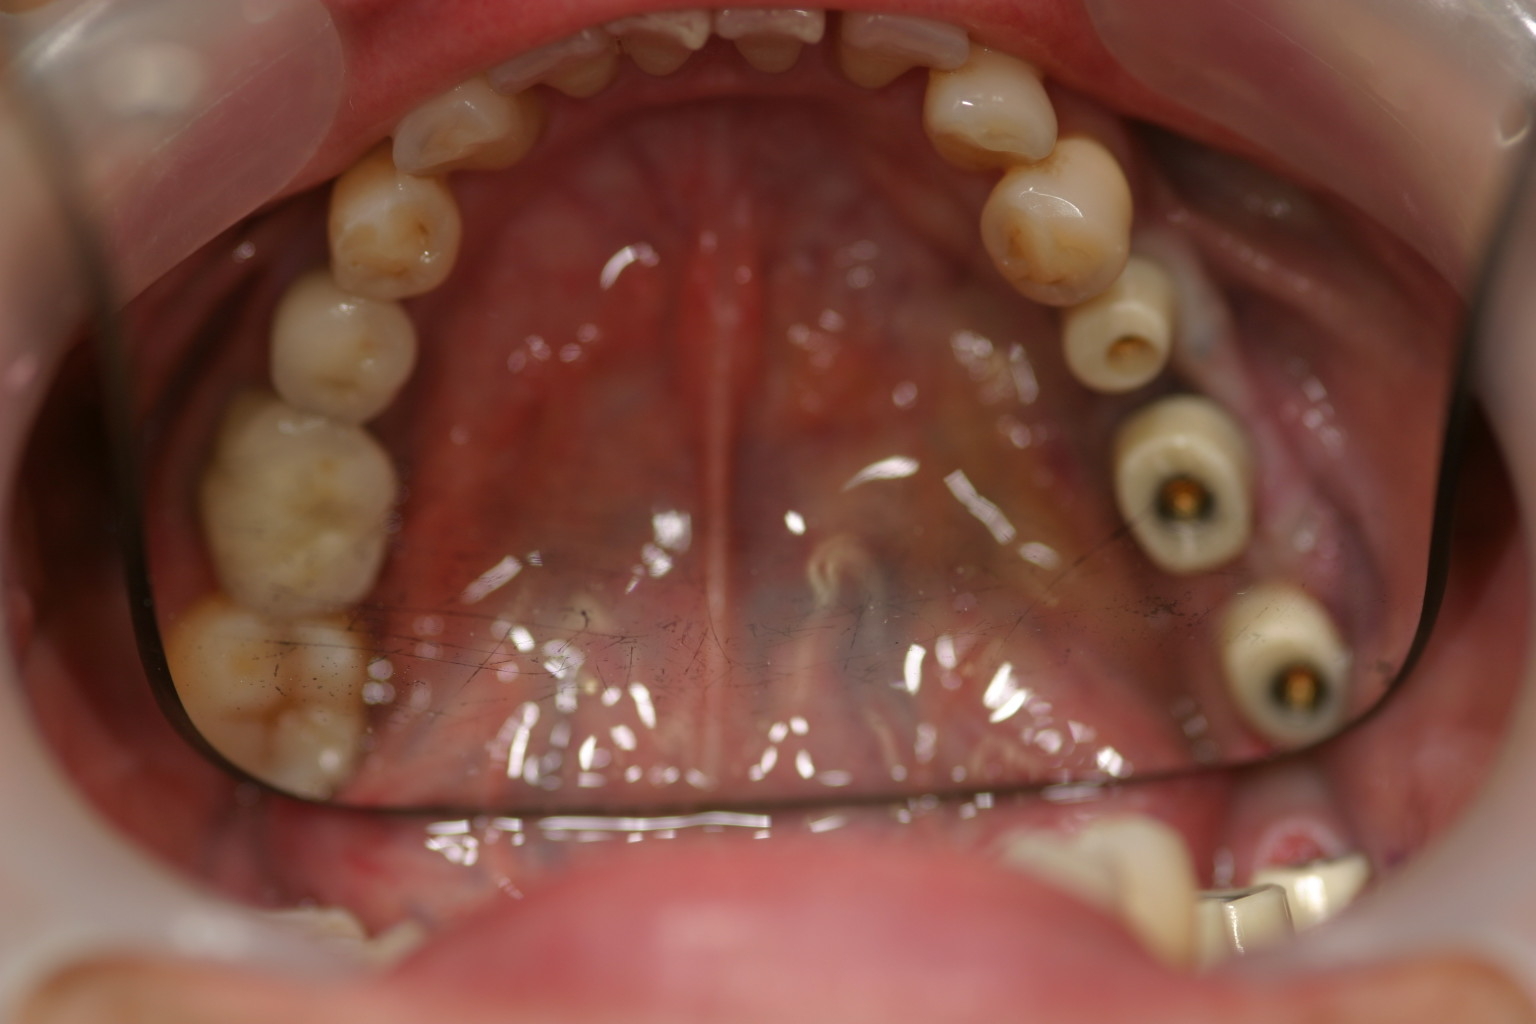

左下567番インプラントジルコニアアバットメント及びジルコニアセラミッククラウン装着